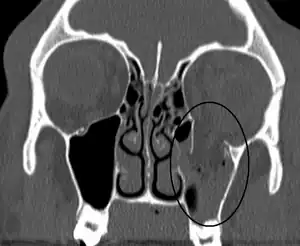

An orbital blowout fracture of the floor of the left orbit.

Thin cut (2-3mm) CT scan with axial and coronal view is the optimal study of choice for orbital fractures.[14][15]